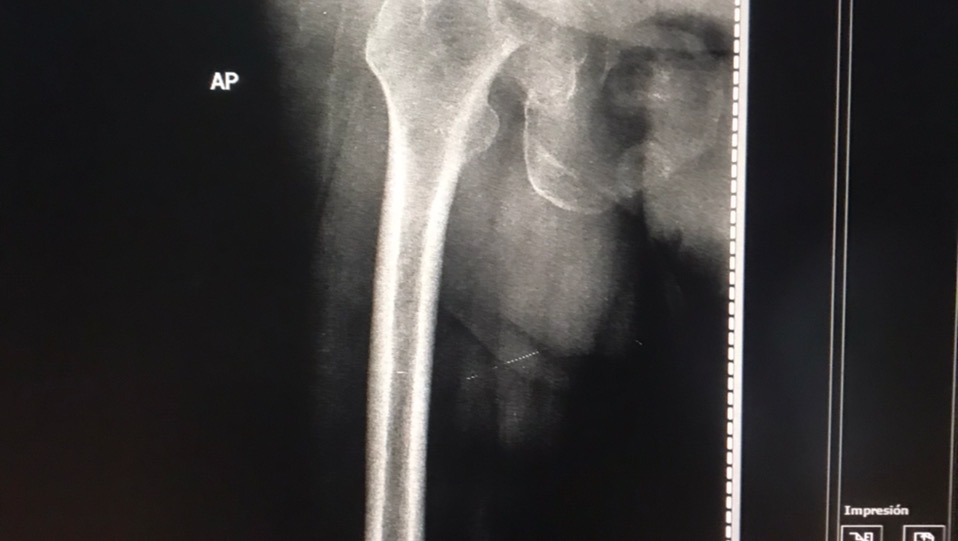

El motivo de esta campaña es para ayudar a la mamá de mi mejor amiga (Maria Alejandra Cáceres). Su mamá, la señora Ida Rincón, el 15 de diciembre, se presentó en la consulta de un traumatólogo en la ciudad de Maracaibo, por presentar un fuerte dolor en la entre pierna. Sorpresa para sus familiares cuando los resultados de los rayos X mostraron una fractura en la cabeza del fémur, y la única forma de solventar el problema es con una prótesis de cadera total derecha.